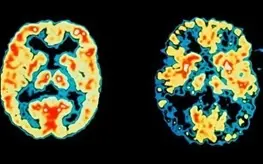

به منظور انجام این تحقیق، اسکن‌های مغزی و آزمون‌های حافظه بر 85 بیمار آلزایمری صورت گرفت. 45 نفر از این افراد آلمانی و ایتالیایی صحبت می‌کردند و بقیه تنها یک زبان ایتالیایی را صحبت می‌کردند.

در واقع افراد دوزبانه ارتباط عملکردی بهتری را در قسمت‌های جلوی مغزی دارند، این قسمت‌ها در حفظ مهارت تفکر در زمان آلزایمر به فعالیت خود در افراد دوزبانه ادامه می‌دهند.